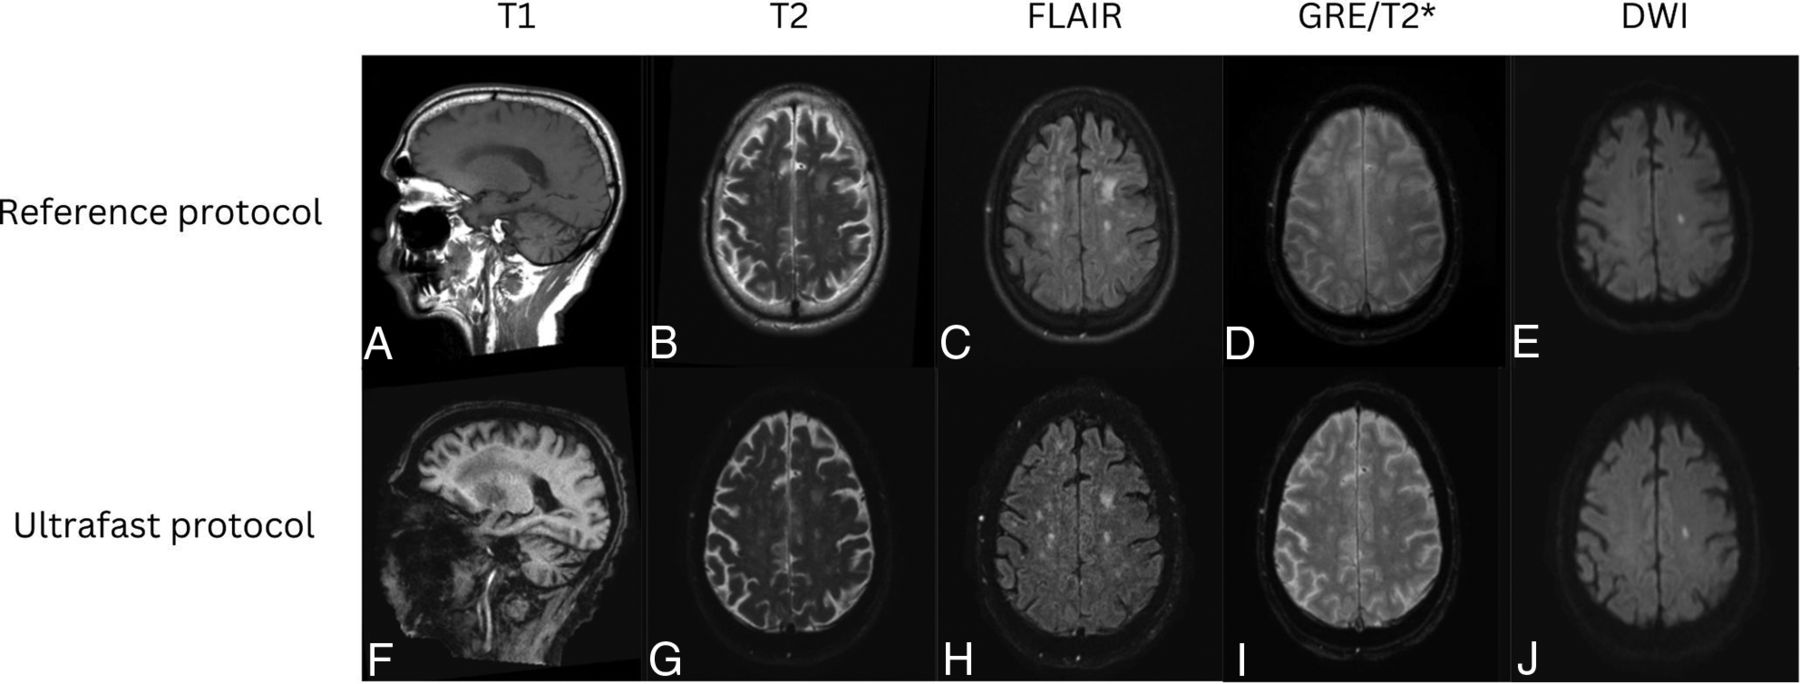

Representative images from 4 clinical cases are shown in Figures 3⇓⇓–6, demonstrating similar diagnostic quality between the ultrafast brain MR protocol images and the reference brain MR protocol images. Figure 3 shows a case of amyloid angiopathy with scattered foci of microhemorrhages. There is blurring of the findings on the reference GRE sequence due to motion artifact, and the foci of susceptibility signal are better appreciated on the ultrafast T2* images. Figure 4 shows a case of herpes simplex virus encephalitis with T2/FLAIR hyperintensity and restricted diffusion in the left greater than right mesial temporal lobes, visualized equally well on both the reference and the ultrafast brain MR protocols. Figure 5 shows a case of punctate subacute infarct in the left centrum semiovale on a background of chronic small vessel ischemic disease, visualized equally well on both the reference and the ultrafast brain MR protocols. Figure 6 shows a case of glioma involving the left thalamus with both the reference and the ultrafast brain MR protocol demonstrating ill-defined T2/FLAIR hyperintensity centered in the left thalamus.

Patient with a diagnosis of herpes simplex virus encephalitis. Reference sagittal T1-weighted (A), axial T2-weighted (B), FLAIR (C), SWI (D), and DWI (E) show prominent T1 hypointensity and T2/FLAIR hyperintensity in the left greater than right mesial temporal lobes with scatter foci of susceptibility signal in the left temporal lobe consistent with microhemorrhages. There was associated restricted diffusion in the left greater than right mesial temporal lobes. These signal abnormalities were all seen with similar conspicuity on the ultrafast sagittal T1-weighted (F), and axial T2-weighted (G), FLAIR (H), SWI (I), and DWI (J).